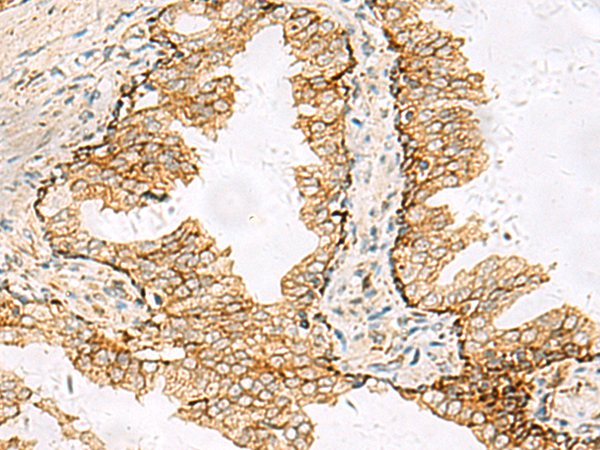

分类: 科研抗体货号: P03162别名: XE7; 721P; XE7Y; CCDC133; CXYorf3; PRKA17A; SFRS17A; AKAP-17A; DXYS155E应用: IHC反应种属: Human